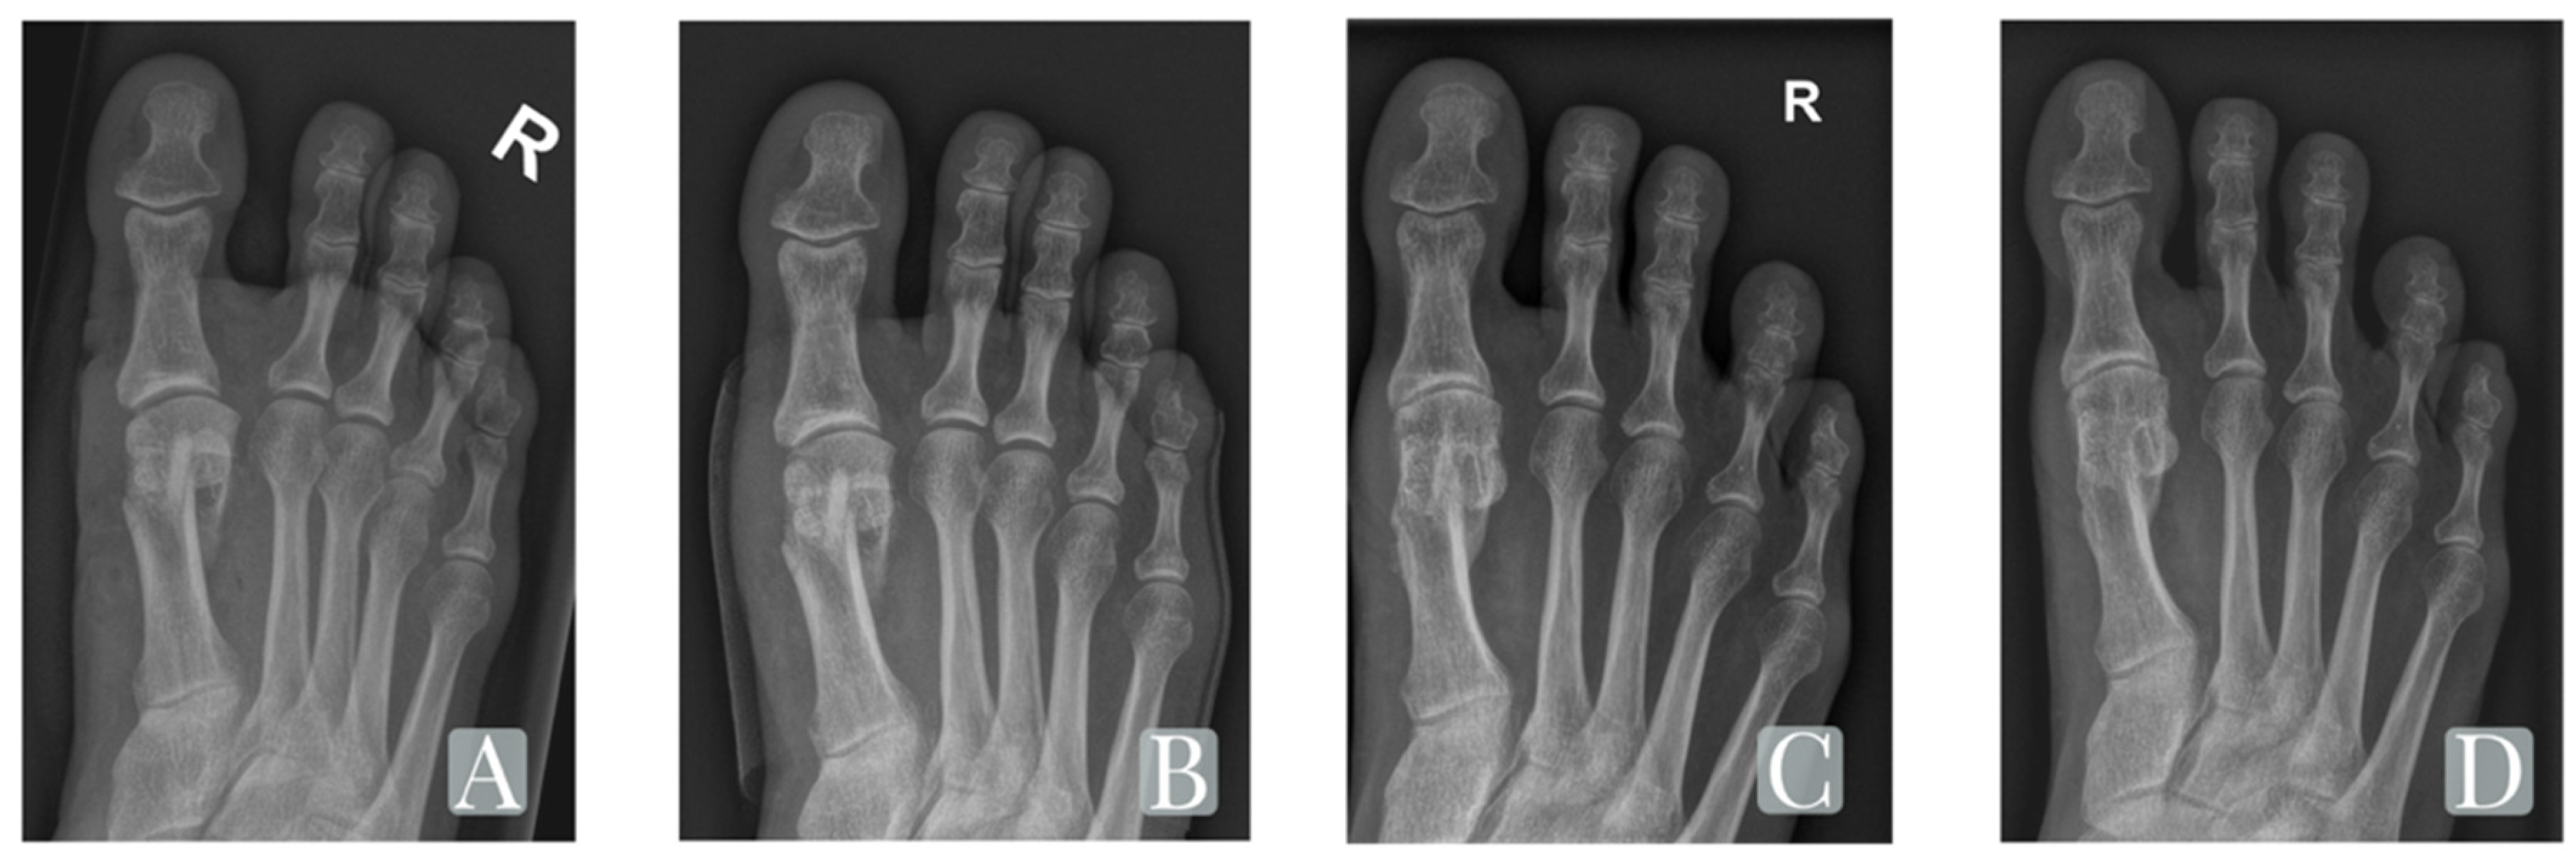

| IM-Angle | 12.6° (±3.2°) | 4.8° (±1.3°) | 5.9° (±1.9°) | <0.001/<0.001 |

| HV-Angle | 24.8° (±4.9°) | 7.2° (±4.4°) | 9.9° (±7.0°) | <0.001/<0.001 |